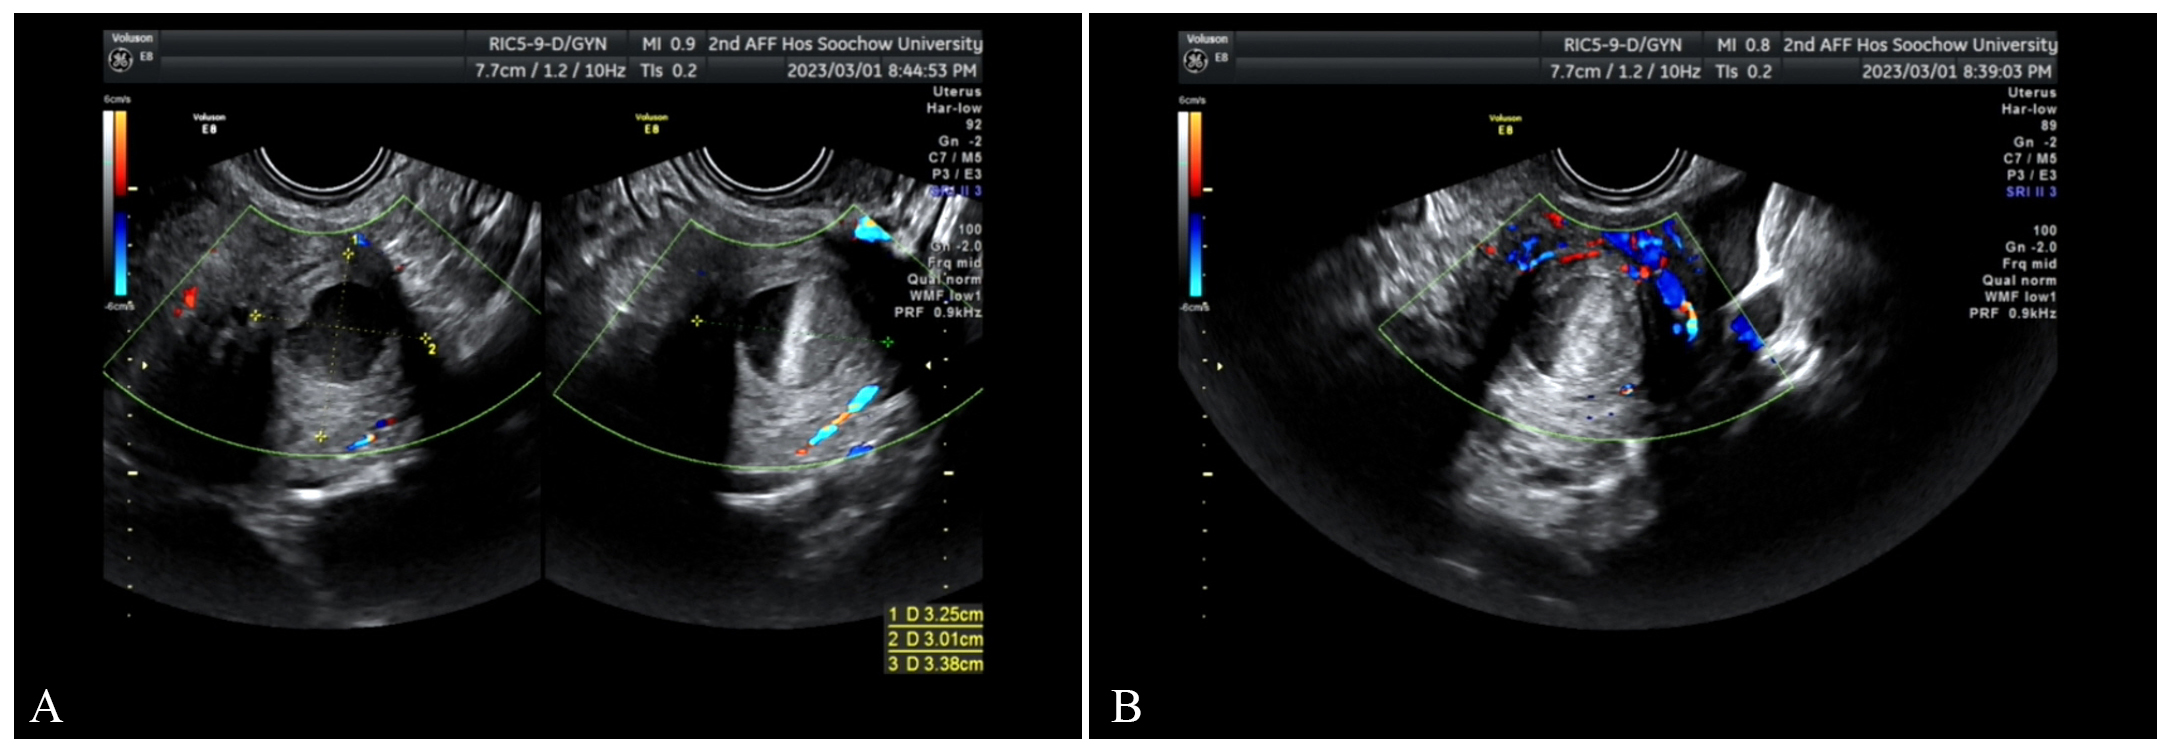

Fig. 3.

March 1, transvaginal ultrasound scan. (A) The mass has enlarged compared with previous findings. (B) The surrounding blood flow signals have increased.